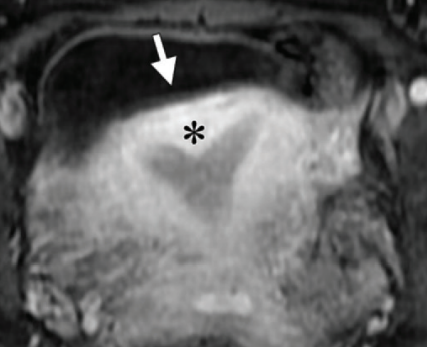

Uterus Septé

Bicorne VS Septé